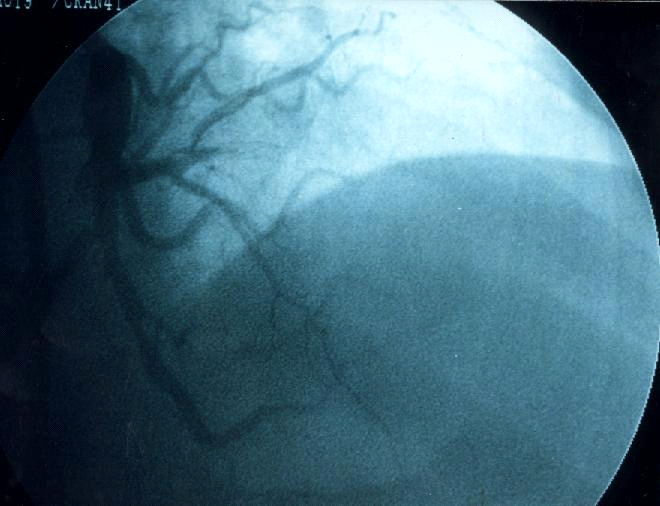

Hình 3-1. NMCT sau dưới cấp.